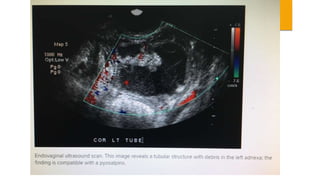

 SONOGRAPHY- Dilated and fluid-filled tubes, fluid in the pouch of

doughlas or adnexal mass are suggestive of PID.

 SONOGRAPHY- Dilatedand fluid-filled tubes, fluid in the pouch of doughlas or adnexal mass are suggestive of PID.  CULDOCENTESIS- Aspiration of peritoneal fluid and its white cell count, if exceeds 30,000/mL. is significant in acute PID. Bacterial culture from the fluid is not informative because of vaginal contamination.